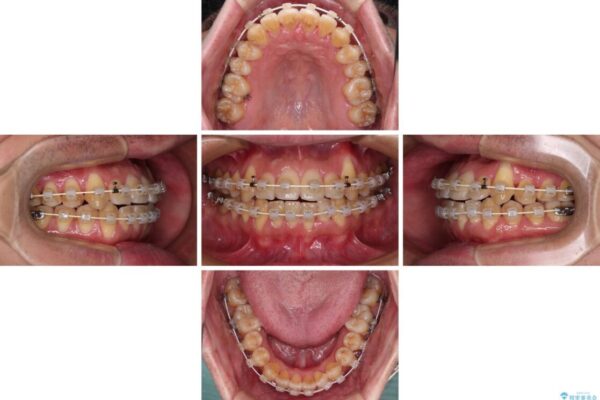

治療途中

• 八重歯とクロスバイト 目立たないワイヤー装置で矯正治療 治療途中画像